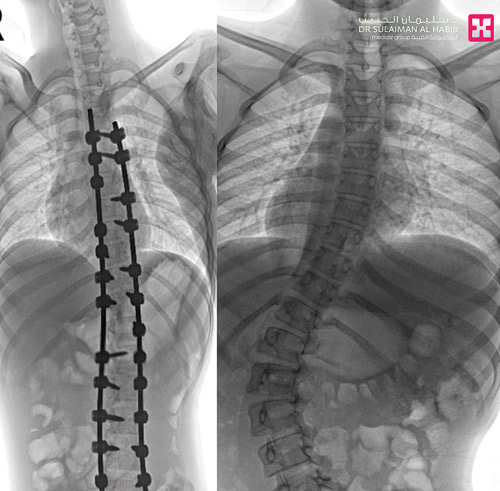

وقال د. خليفة إن المريض قدم إلى المستشفى من الكويت وهو يشتكي من انحناء جانبي للعمود الفقري ومن تحدب وميلان شديد للحوض أدى إلى صعوبة كبيرة للعناية به ومعاناة في الجلوس المستقيم. وقد أدت هذه الأعراض إلى تغيير نمط حياته وتقييد حركته. وفور وصوله إلى المستشفى أجريت له التحاليل والفحوصات الطبية الدقيقة، التي بينت إصابته بحالة انحراف «جنف» فوق الـ»60» درجة وميلان بالورك، ودرس الفريق الطبي الحالة على ضوء نتائج الفحوصات والتحاليل، وخلص إلى ضرورة التدخل الجراحي لعلاج العيوب، والحد من المضاعفات. وبعد اتخاذ التدابير المناسبة لمثل هذه الجراحات المعقدة أجريت للمريض عملية جراحية استمرت زهاء 6 ساعات تم فيها تقويم العمود الفقري بعدد 26 من البراغي المعدنية وتثبيت ودمج الفقرات، واستخدمت في العملية مجموعة من أحدث الأجهزة الطبية التي ساهمت مع الكوادر الطبية عالية الكفاءة والتأهيل بالمستشفى في نجاحها، ولله الحمد.

وأضاف د. الخليفة أن المريض بقي منوماً قيد العناية الطبية الحثيثة بالمستشفى لأيام عدة، تحسنت خلالها حالته الصحية باضطراد، وتحسن وضع الجلوس واستقامة الظهر، وأيضاً قدرته على الاستلقاء والنوم على ظهره، بعد تعديل وضعية الحوض والكتف، وخرج من المستشفى وهو بصحة جيدة إلى مركز التأهيل الطبي ليستكمل برنامجه للعلاج التأهيلي.